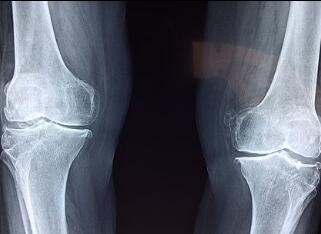

妈妈看龙龙平静的样子,继续说道:“任何东西有有害的一面,就会有对人有利的一面,好坏不是东西自身的特点,要看是什么人在用,用在哪儿。就像炸药,既能伤人,也能炸掉山头修路。X射线也是这样,有些医学诊断特别是骨科,就特别需要X射线帮忙,才能确定病人到底是哪块骨头断了,哪里发生骨折。”